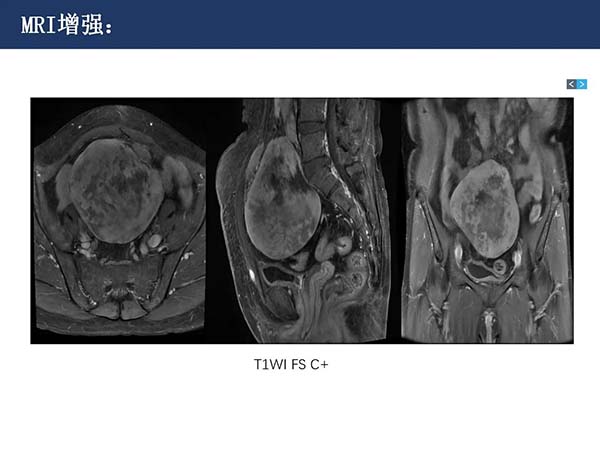

【杨柳病例】腹盆腔韧带样纤维瘤病